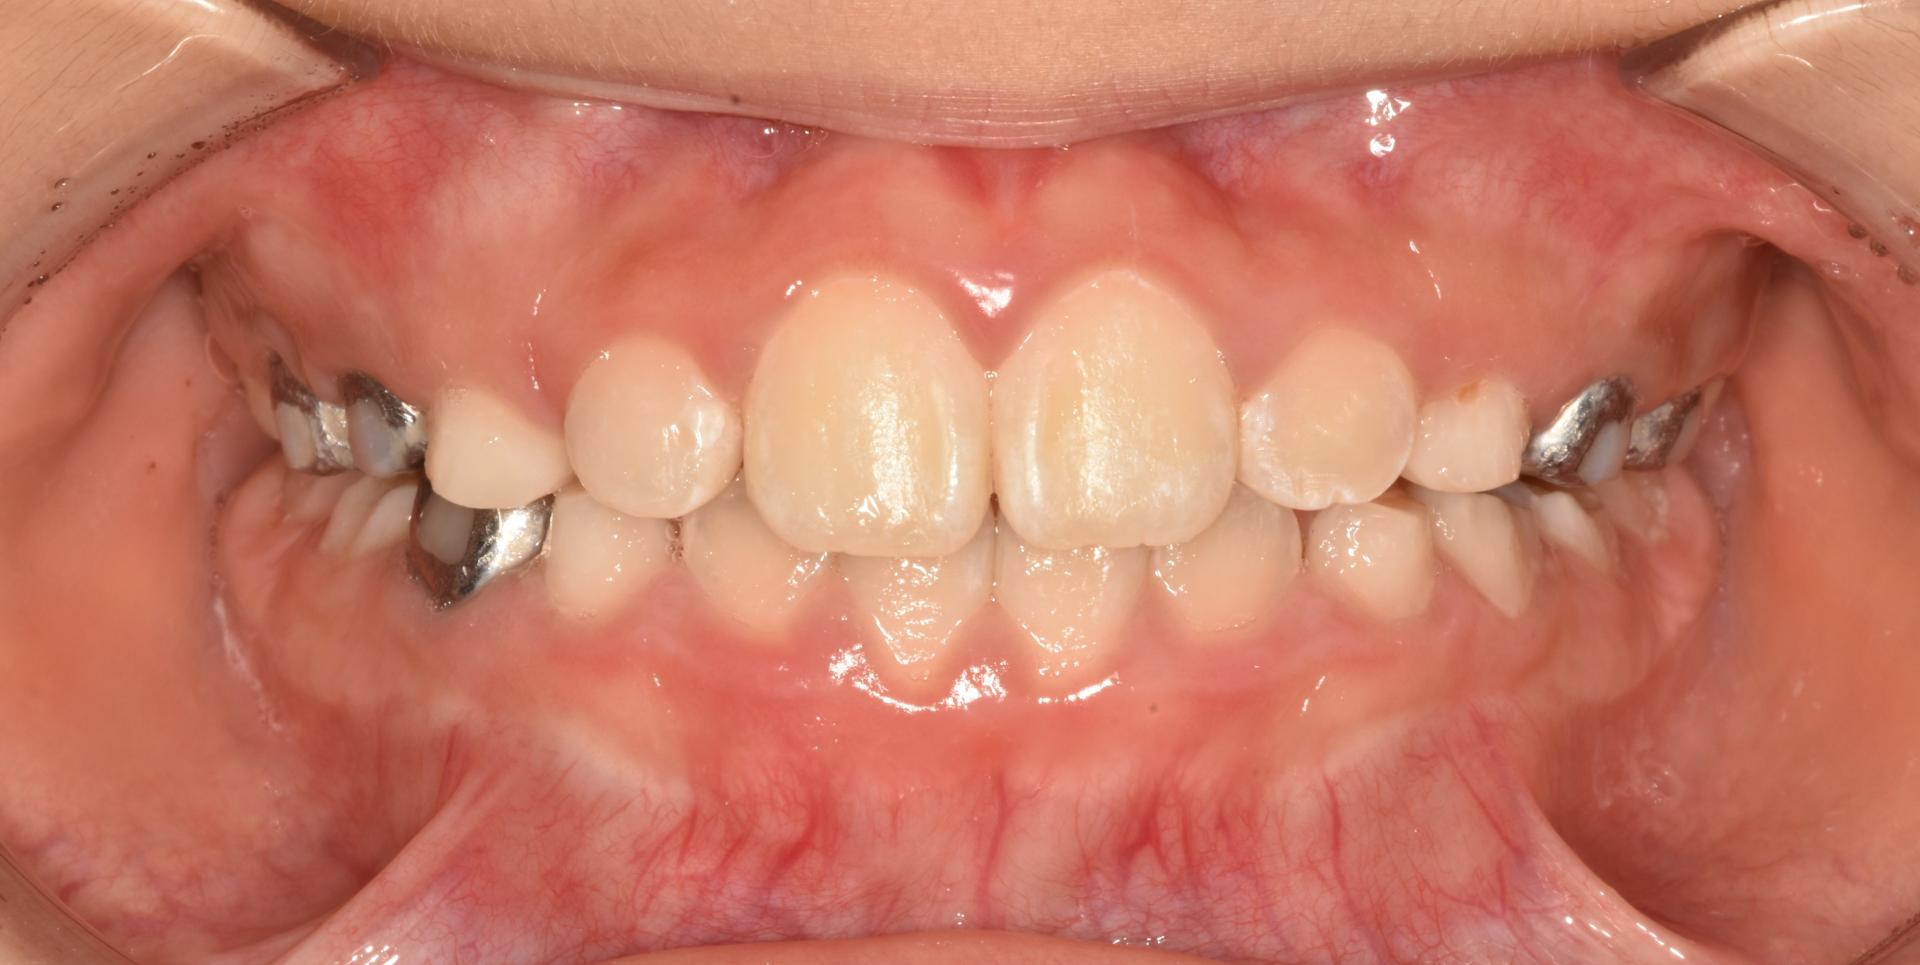

1년 후, 교정완료하였습니다. 튀어나온 앞니는 가지런히 넣었고 악궁을 확장하여 충분한 송곳니, 어금니의 맹출공간을 확보하였습니다.

치료개시일 : 2024.05.24. 치료종료일 : 2025.05.16. |

치료개시일 : 2024.05.24.

치료종료일 : 2025.05.16.